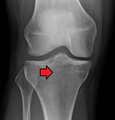

Lipohemarthrosis (presence of fat and blood from bone marrow in the joint space after an intraarticular fracture) seen on X-ray in a person with a subtle tibial plateau fracture

Lipohemarthrosis due to a tibial plateau fracture

Subtle tibial plateau fracture on an AP X ray of the knee

Lipohemarthrosis due to a tibial plateau fracture- A tibial plateau fracture seen on X-ray